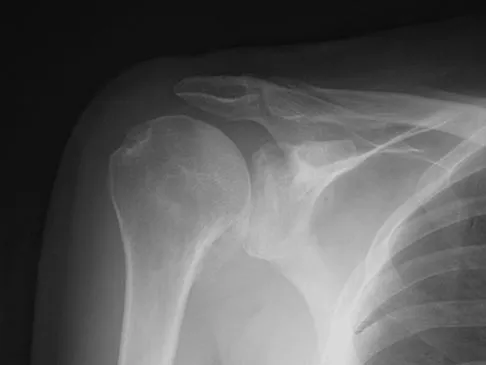

A 47-year-old male tennis player has pain in his nondominant shoulder that has failed to respond to 4 months of nonsurgical management. Examination reveals acromial tenderness and pain at the supraspinatus tendon insertion. He has a positive impingement sign, pain on forward elevation, and minimal cuff weakness. The MRI scans are shown in Figures 30a and 30b. To completely resolve his symptoms, treatment should consist of

The MRI scans show a mesoacromion with tendonopathy of the supraspinatus. The history and physical findings indicate that the patient has a symptomatic os acromiale. Simple excision of the unstable os acromiale has not yielded consistently good results. Meticulous internal fixation using tension banding with cannulated screws and autologous bone grafting has shown good results for this problem. Hutchinson MR, Veenstra MA: Arthroscopic decompression of shoulder impingement secondary to os acromiale. Arthroscopy 1993;9:28-32.

- Warner JJ, Beim GM, Higgins L: The treatment of symptomatic os acromiale. J Bone Joint Surg Am 1998;80:1320-1326.